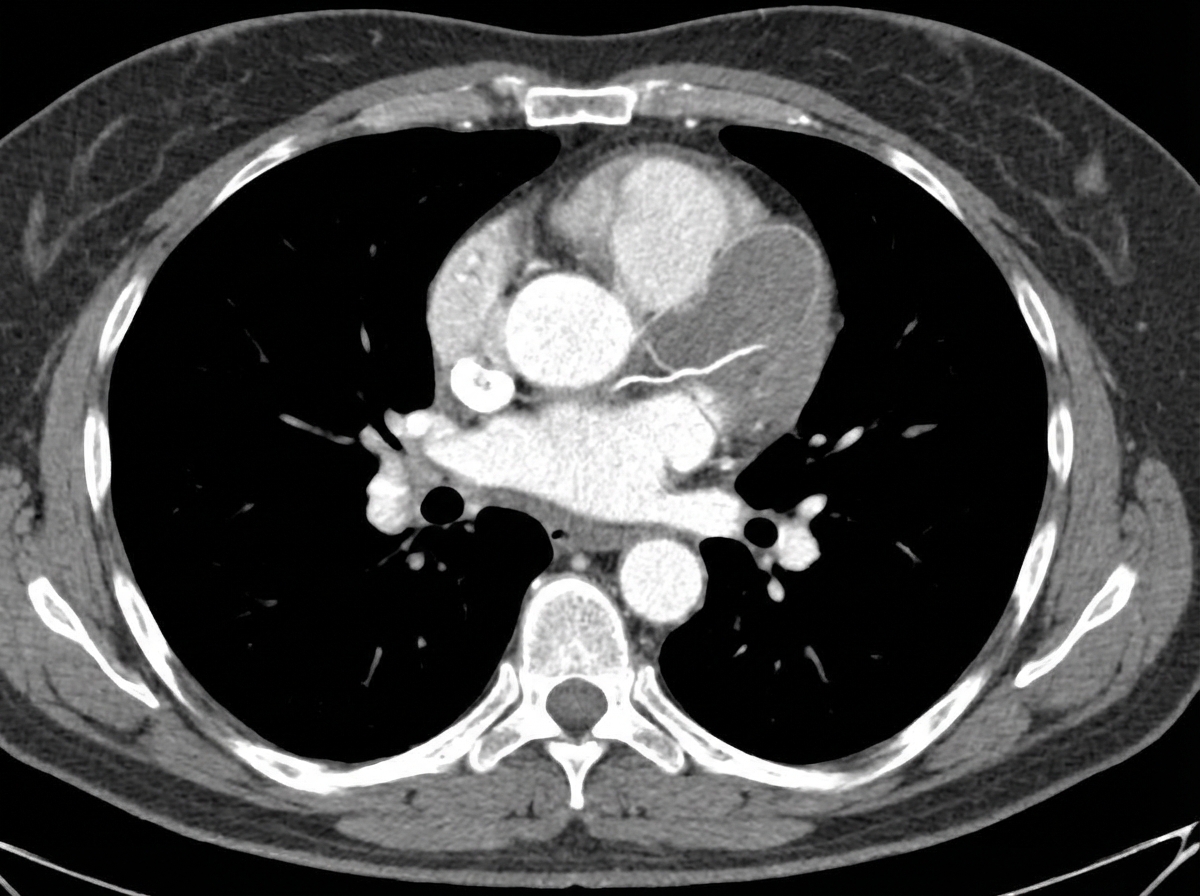

A 58-year-old man is brought to the emergency department by his wife 30 minutes after the sudden onset of severe retrosternal chest pain radiating to his back. He has a history of hyperlipidemia, hypertension, and type 2 diabetes mellitus. He has smoked one-half pack of cigarettes daily for 20 years. Medications include aspirin, captopril, atorvastatin, and metformin. His pulse is 80/min and blood pressure is 160/60 mm Hg. A CT scan of the chest is shown. Which of the following is the strongest predisposing factor for this patient's current condition?